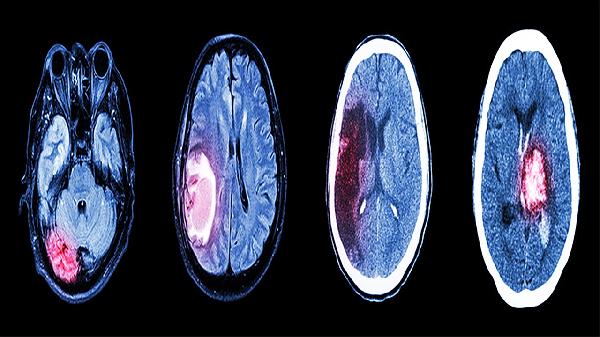

适用于脑外伤或手术后恢复期的认知康复,能减轻脑缺氧导致的思维混乱。但脑梗死急性期、癫痫发作期禁用,用药期间需要定期监测肝肾功能,儿童用量须严格遵医嘱调整。